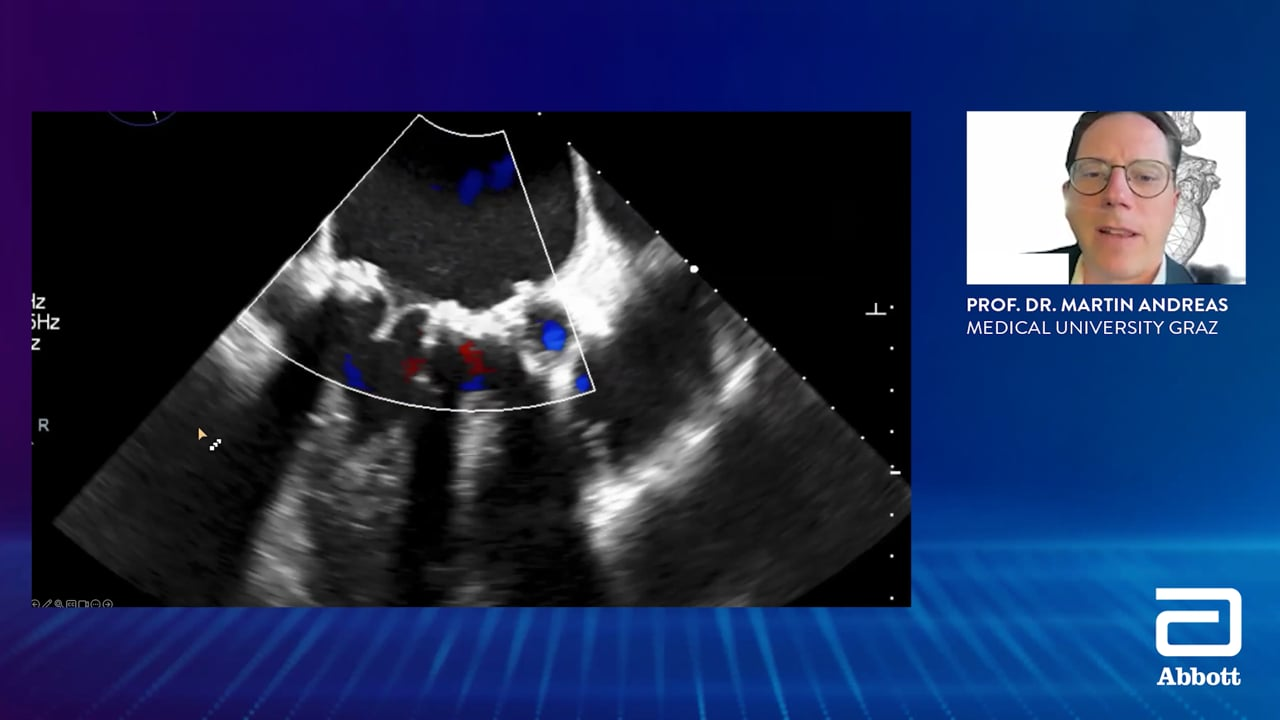

Advancing Mitral Valve Replacement: Delivering durability, Implantability and a path for future interventions